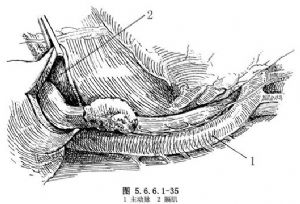

(1)切口。患者取右侧卧位,行左胸后外侧切口,经第6肋床或肋间进胸。

(2)用常规方法游离肿瘤。切开膈肌并游离胃(图5.6.6.1-35)。将胃管向外牵拉,当其尖端到达食管预定切除部上方3cm左右后重新固定。